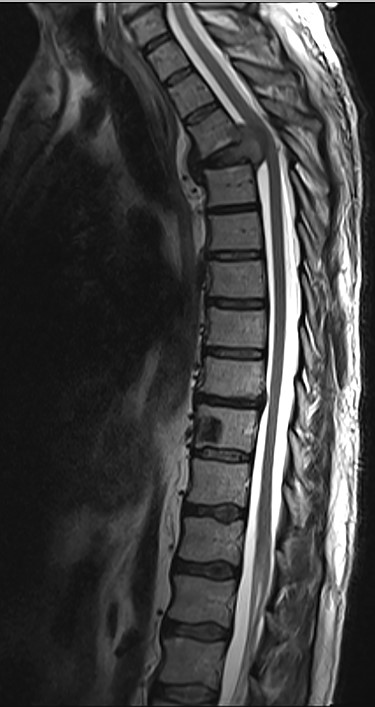

Spinal images are presented in Figs 1–6. Cross-sectional imaging revealed no other neoplastic lesion. He received dexamethasone 10 mg bolus then 4mg four times daily with appropriate proton pump inhibitor coverage. Due to no distinguishable major arterial feeder upon review of the imaging jointly with the neuroradiologist, pre-operative embolization was not attempted. The following morning, he underwent posterolateral right costotransversectomy, ligation of the ipsilateral T4 nerve root, T4 vertebrectomy and insertion of an expandable titanium cage with T1–T7 pedicle screw fixation (Figs 7 and 8). Post-operatively his pain improved to VAS 2/10 and motor power in his left lower limb improved to MRC grade 4/5. The patient was discharged home Day 10 post-admission with physiotherapy.

Sagittal T2-weighted magnetic resonance image (T2W MRI) with T4 metastatic epidural spinal cord compression (MESCC) and a synchronous T10 lytic lesion.